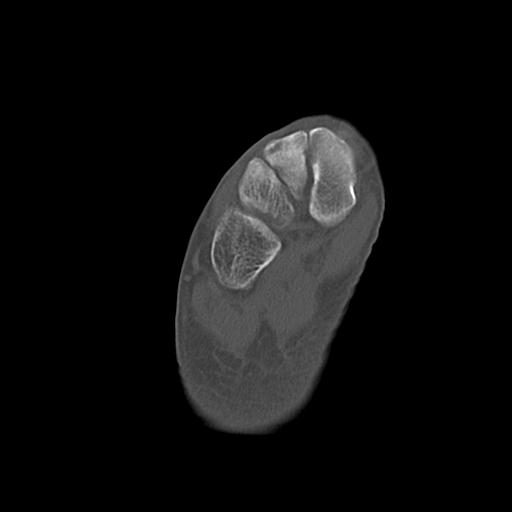

49554 3/13 膝 4R 3/16 4R 1/18 2R 78歳男性 膝蓋骨骨折